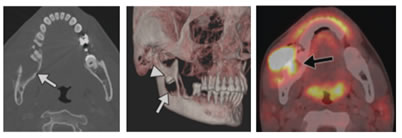

3. Keratocystic odontogenic tumor (KCOT, formerly OKC): It originates from the dental lamina. It has a thin wall of keratinized epithelium and may contain a thick cheesy material formed by the desquamated keratinized epithelium. These contents sometimes increase the radiographic attenuation of the cyst at CT (Fig. 7), but this does not occur on panoramic tomography. The commonest affected age of The KCOT is the second and third decades. It occurs commonly in the posterior mandible (90% posterior to the canines, 50% in the ramus). Similar to odontogenic lesions, its epicentre is above the inferior alveolar canal. In 40% of cases it is related to an unerupted tooth, thus it should be considered in the differential diagnosis of the dentigerous cyst. It usually has a well-defined corticated outline that may be scalloped. It produces slight jaw expansion and is less likely to cause displacement or resorption of the teeth root than the dentigerous cyst. It may reach a large size and has a high recurrence rate after surgical removal. The basal cell nevus syndrome (Gorlin-Goltz syndrome) is characterized by Multiple KCOTs, vertebral and rib anomalies and heavy calcification of the falx cerebri.13 A keratocystic odontogenic tumor is a benign but locally aggressive odontogenic tumor that is most commonly occurs in the ramus and body of the mandible. It may be unilocular or multilocular and often contains daughter cysts that extend to the surrounding bone leading to mild bulging of the cortex but without marked cortical expansion. Keratocystic odontogenic tumor shows slight to no expansion within the body of the mandible; however, once it reaches the ramus, it typically causes significant expansion. It may show a more aggressive growth pattern including multilocularity, cortical expansion, perforation of the cortical bone, tooth and mandibular canal displacement, root resorption, and extrusion of erupted teeth (Fig. 8).14 CT shows a unilocular or multilocular cyst with corticated margins. Keratocystic odontogenic tumors typically occur in the mandibular body and ramus in association with an impacted tooth.13 MRI shows a thin-walled, minimally peripherally enhancing cyst with heterogeneous intensity fluid contents (intermediate T1 signal and intermediate to high T2 signal) due to variable proteinaceous content. MRI can help differentiate between keratocystic odontogenic tumor and ameloblastoma, the latter of which has a mixed pattern of cystic and solid and components, irregular thick walls, and avid enhancement of solid components. Rarely, malignant transformation into squamous cell carcinoma occurs; PET/CT will visualize intense FDG hypermetabolism similar to other head and neck squamous cell carcinomas (Fig. 9).15

7

Figure7: Odontogenic keratocystic tumor (KCOT) in the maxilla. Axial CT section shows well-defined cyst centred in posterior right maxilla (white arrow heads), with amorphous hyper attenuating central contents (black arrow).

8

Figure 8: Keratocystic odontogenic tumor. (A) Oblique sagittal CT image demonstrates large radiolucent mass (arrows) in posterior body of mandibular ramus, with scalloping of cortex. (B) Axial contrast-enhanced CT image demonstrates cystic mass with mild peripheral enhancement (arrow) breaking through cortex and extending into left masseter muscle.

9

Figure 9: squamous cell carcinoma most likely originating on top of keratocystic odontogenic tumor. (A) Axial and (B) 3D CT images obtained using bone algorithm show large radiolucent mass (arrows) within posterior body of left mandible with associated cortical break. Note periosteal reaction, which may suggest aggressiveness of lesion or superimposed infection. the mass (arrowhead, B) contains crown of unerupted third molar. (C), Fused PET/CT image shows intense FDG uptake (maximum standardized uptake value = 25.6) associated with left mandibular mass (arrow); this finding suggests malignancy. Bilateral hypermetabolic level II lymph nodes were also noted (not shown).